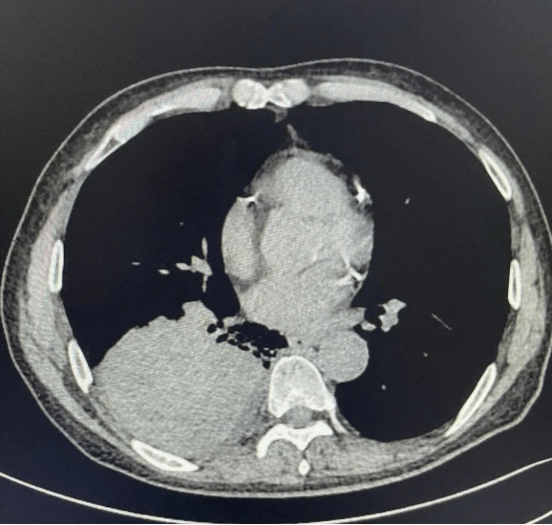

• CT室专家与呼吸团队紧密协作,精准定位,并准确调整穿刺角度,确保穿刺针精准命中病灶。

• 冷冻活检操作中,医护人员细致操作,将完整的病变组织顺利取出,为病理诊断提供坚实保障。